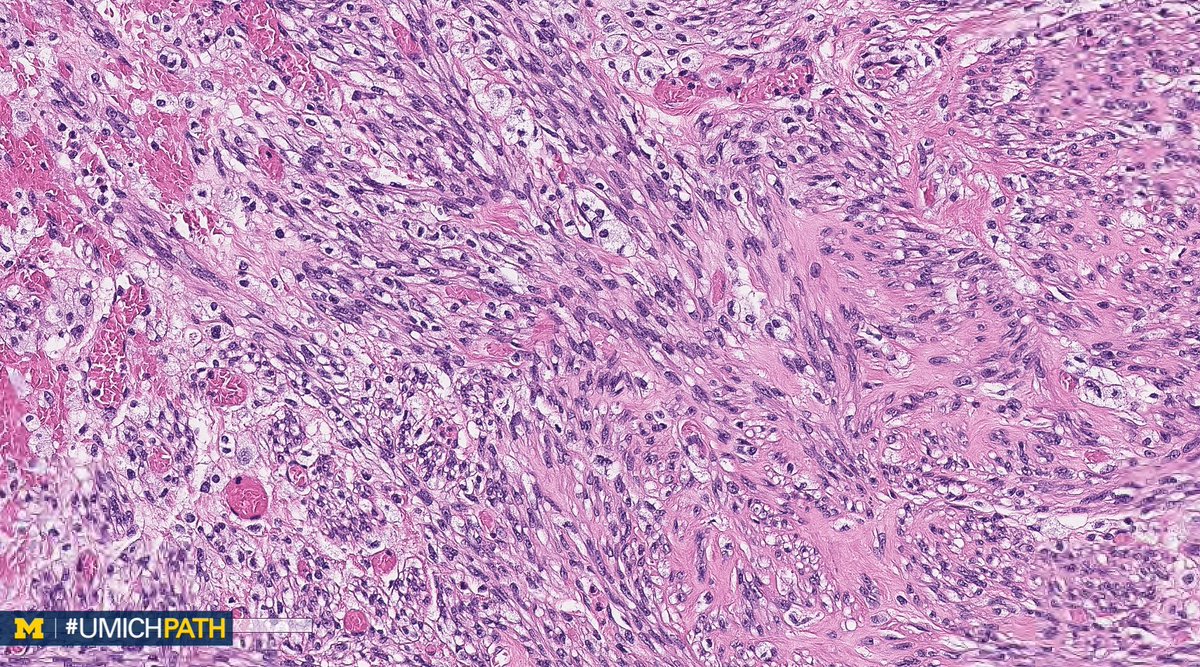

What’s your #DailyDx of this pelvic peritoneum biopsy, post radical cystectomy? What immunoprofile and histologic characteristics would you expect? We will tweet the answers and some quick facts later this week! #UmichPath | @MiPathKunju

What immunoprofile and histologic characteristics would you expect?

We will tweet the answers and some quick facts later this week!

#UmichPath | @MiPathKunju

Ready for the answers to this #DailyDx case? Here we go! What you are seeing is a Plasmacytoid Urothelial Carcinoma. #UmichPath | @MiPathKunju

A: PEComa. A rare tumor with perivascular epithelioid cell differentiation. Aggressive behavior predicted by size >5 cm, infiltrative growth, hypercellularity, mits (>1/50 HPF), high-grade nuclei, and necrosis. IHC: Positive for sm. muscle & melanocytic markers. #GYNPath #DailyDx

UMichPath's tweet image. A: PEComa. A rare tumor with perivascular epithelioid cell differentiation. Aggressive behavior predicted by size >5 cm, infiltrative growth, hypercellularity, mits (>1/50 HPF), high-grade nuclei, and necrosis. IHC: Positive for sm. muscle & melanocytic markers. #GYNPath #DailyDx